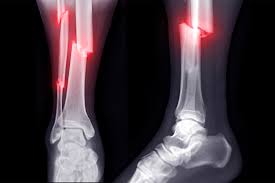

• Orthopaedic reconstruction: Once the patient is stable, orthopaedic injuries are addressed. This can include external or internal fixation of fractures, joint realignment, soft-tissue reconstruction and staged surgeries for open or contaminated wounds. Early fixation where appropriate helps reduce complications and facilitates rehabilitation.

Pelvic fractures with associated organ injury, multiple long-bone fractures, open fractures with severe soft-tissue loss, and distal tibial (Pilon) fractures are typical examples.